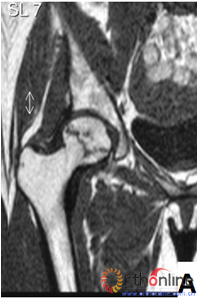

图2-1

图2-2

图2-3

图2 依据股骨头外侧柱存留情况,股骨头坏死的分型。(图2-1)分为Ⅰ型(外侧柱全部存留)(A)MRI图像显示;(B)7年后CT显示股骨头仍未塌陷;(图2-2)Ⅱ型(外侧柱部分保留)(A)MRI显示外侧皮质存留;(B)4年后CT显示股骨头仍未塌陷;(图2-3)Ⅲ型(坏死带穿透股骨头);(A)MRI显示坏死带;(B)2年后股骨头塌陷

Fig 2 According to preservation of the lateral pillar, the necrosis was divided into three types. (Fig 2-1)Type Ⅰ: Whole lateral pillar preserved (A) MRI showing; (B) no collapse occurred seven years later by CT showing. (Fig 2-2)Type Ⅱ: Preservation of the partial lateral pillar, (A) MRI showed the preservation of the lateral cortical bone; (B) no collapse of the femoral head four years by CT. (Fig 2-3)Type Ⅲ: the necrotic line pass through the cortical bone and bone morrow ;(A) MRI showed the necrotic line; (B) collapse of the femoral head occurred two year later.